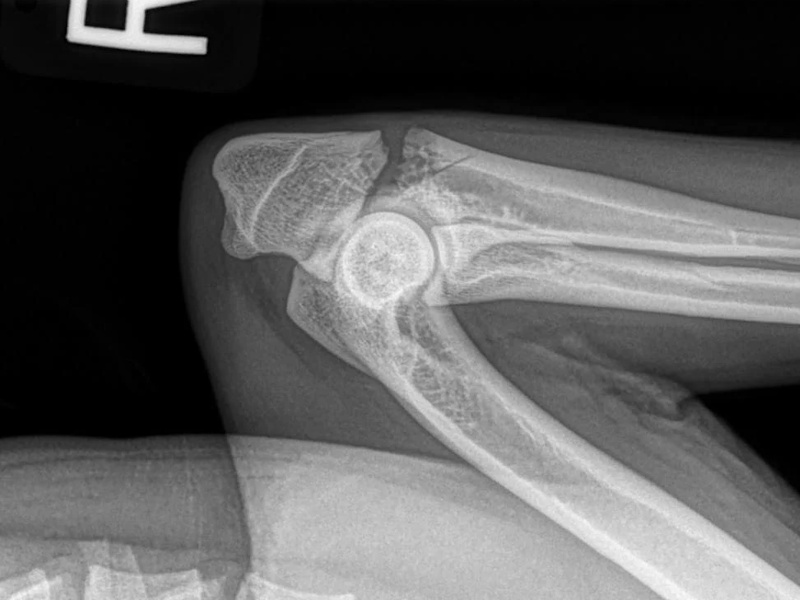

Patellar Luxation

Diagram of a Patella Luxation

Surgical Treatments for Patellar Luxation

- Tibial Tuberosity Transposition

- Femoral Varus Osteotomy

- Recession Sulcoplasty

- Soft Tissue Reconstruction